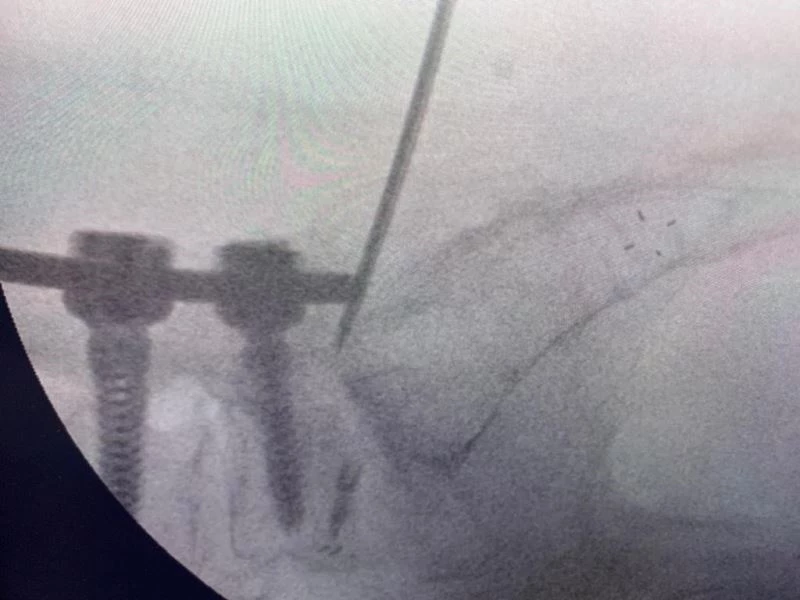

Hekimler; kırıklar, skolyoz eğrilikleri, tümörler, kanal daralması gibi ameliyatlarında vidalarla omurları desteklemede bulunuyor. Ancak vidaların bulunduğu omurlar düşme, çarpma gibi kazalar nedeniyle kırılabiliyor. Bu duruma müdahale etmek için ise açık ameliyat gerekiyor. Beyin ve Sinir Cerrahisi Uzmanı Prof. Dr. Kemal Yücesoy, vidalı omurganın kırığına dünyada ilk kez transforaminal transdiskal yaklaşımla sement desteği yaptı. Geliştirdiği yöntem, nöroşirürji alanında dünyanın en prestijli dergilerinden olan World Neurosurgery’nin son sayısında yayımlanarak literatüre girdi. Hastaların sadece 5 dakikasını alan ve 2 saat sonra günlük hayatına dönmesini sağlayan yöntem, Türkiye’ye gurur yaşattı.

Uzun süre, vidayı çıkarmadan kemik çimentosunu koyma konusunda çalışmalar yaptığını belirten Prof. Dr. Yücesoy, “Kapalı bel fıtığı ameliyatlarında iğneyle sinirin altına girerek izlediğimiz bir yol var. ‘Hastaların kemiğinin içine bu yoldan girilebilir’ diye düşündüm ve bunu da uygulamaya başladım. Bu yöntemde, hastaya lokal anestezi uyguluyoruz. Kıkırdağın olduğu bölümden diskin içine iğneyle girip oradan da kemiğin içine ulaşıyoruz ve çimentoyu koyuyoruz. Bu daha önce hiç uygulanmamış bir yol. Kırılmış vidalı bir kemiğe ilk kez o vidayı çıkarmadan kapalı yöntemle girip müdahale etmiş olduk” diye konuştu.